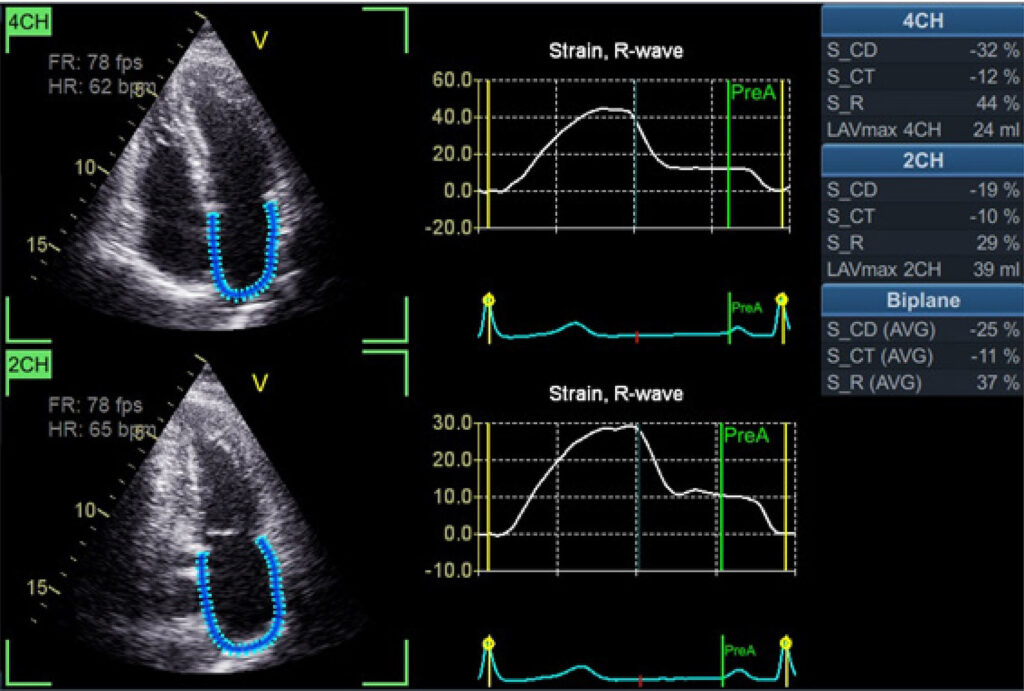

As doenças cardiovasculares (DCV) são a principal causa de morte no Brasil, com o envelhecimento sendo um grande fator de risco. Estudos indicam que a prevalência de DCV aumenta com a idade, afetando a hipertrofia ventricular, disfunção diastólica e fibrilação atrial. A miopatia atrial, relacionada ao envelhecimento, tem sido mais estudada, com o estresse oxidativo e a inflamação crônica sendo investigados como agentes causadores desse processo. A função atrial esquerda tem sido mais analisada com destaque para seu papel na performance cardíaca. Técnicas atuais de análise ecocardiográfica, como o speckle tracking, permitem uma avaliação detalhada da função atrial, mostrando vantagens em relação à análise do volume atrial máximo. Estudos revelam a importância do strain atrial na previsão de eventos cardiovasculares. Com o envelhecimento, há uma redução progressiva das funções atriais, e novas medidas estão sendo desenvolvidas para detectar precocemente a disfunção atrial, o que pode impactar as futuras diretrizes e a definição dos padrões normais relacionados à idade.